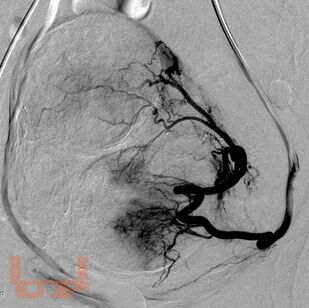

Рентгенэндоваскулярная эмболизация маточных артерий при лечении больных с миомами матки и маточными кровотечениями

Учебно-методическое пособие предназначено для врачей хирургов, лучевых диагностов, эндоваскулярных хирургов, гинекологов. В учебном пособии рассматриваются диагностика, анатомия маточных артерий и особенности кровоснабжения матки и миомы, эндоваскулярное лечение миомы матки и маточных кровотечений стандартным и модифицированным методом.